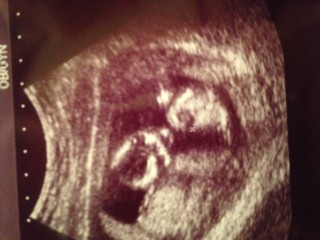

初めての4Dエコーです!

手足もよく写ってかわいい♪

先生が見せてくれている間に

右手を振ってくれました!

4週間ぶりの検診で初4Dでした。

初めて動いているところを見ました。

てか大暴れでした。あんなに動いていてもお腹に感触を感じないのが

なんだか不思議でした^ ^早く胎動感じたい^ ^